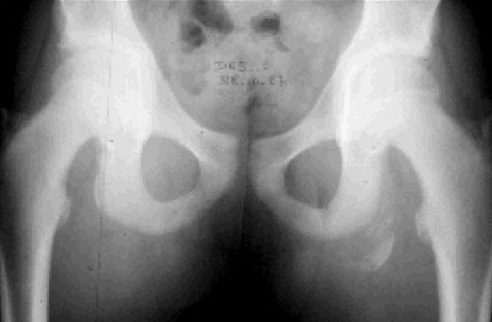

Le bassin, ou ceinture pelvienne, composé des os iliaques, du coccyx et du sacrum, est le socle de la colonne vertébrale et reçoit donc le poids de la partie supérieure du corps. Le bassin, s'articule également avec les fémurs formant l'articulation de la hanche. C’est donc une zone de transmission des pressions, soumis à de fortes contraintes, lors de la marche ou de la course à pied.